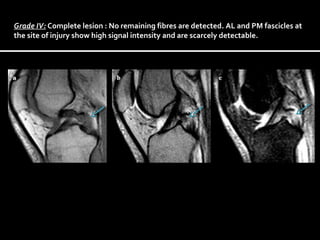

MRI classification was first published by Gross et al.

Grade I : Intraligamentous lesion : High signal intensity within the ligament.

Grade II : Partial lesion: High intensity signal on the dorsal edge of the ligament.

(Anatomical site of the posteromedial fascicle)

Grade III: Partial lesion : High signal intensity on the ventral edge of the ligament.

(The anatomical site of the anterolateral fascicle.)

Grade IV: Complete lesion : No remaining fibres are detected. AL and PM fascicles at

the site of injury show high signal intensity and are scarcely detectable.